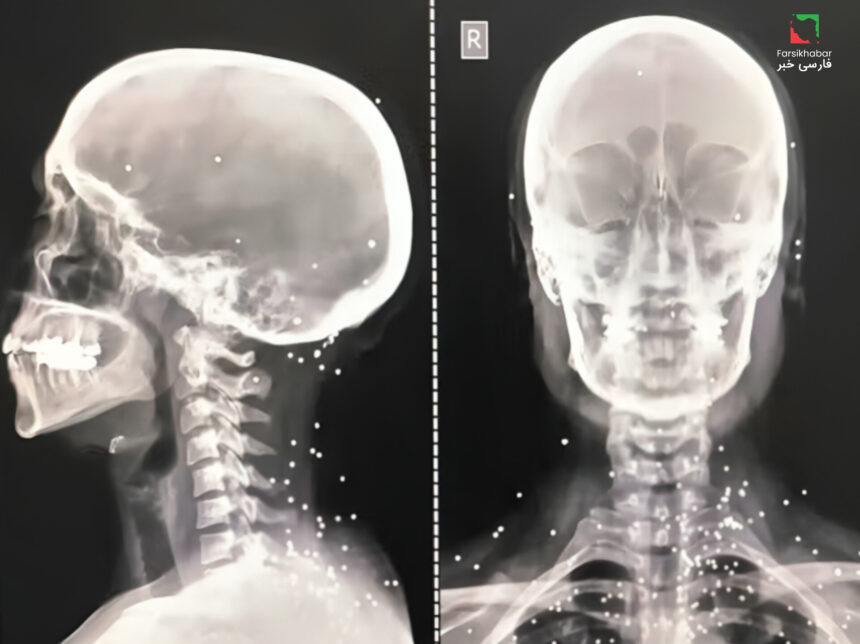

الگوی جراحات شدید و هدفمند

در جریان سرکوب خونین معترضان ایران، تصاویر پزشکی ثبت‌شده نشان می‌دهند که نیروهای امنیتی با گلوله‌های کالیبر بالا و ساچمه‌های فلزی، عمدتاً نواحی حیاتی بدن معترضان را هدف قرار داده‌اند.

این تصاویر، شامل سی‌تی‌اسکن‌ها و رادیولوژی‌های متعدد است که شدت جراحات و پراکندگی گلوله‌ها را به وضوح نشان می‌دهد.

در تصاویر، گلوله‌هایی در گردن، مغز، ستون فقرات و نواحی تناسلی مشاهده شده که پیامدهای طولانی‌مدت جسمی و روانی برای قربانیان به همراه داشته است.